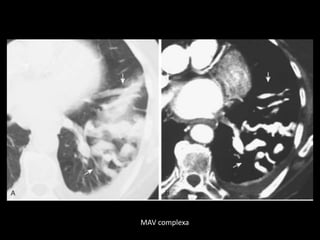

MAV complexa

Malformação arteriovenosa(MAV) TC:o aspecto típico é de uma massa regular, lobulada, redonda ou oval, ou até o de uma formação serpenginosa, com menos de 1 cm a vários cm de tamanho, associada a uma artéria nutriz visivelmente aumentada e uma veia de drenagem alargada; Uma ANGIO-TC geralmente faz o diagnóstico; Tratamento pode ser realizado com terapia embólica.

• 19.